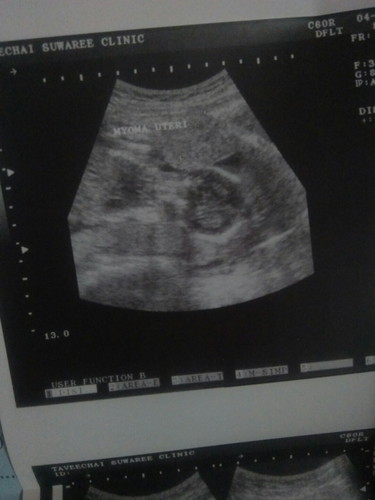

เนื้องอก

มีแม่คนไหนตั้งครรภ์แล้วเป็นเนื้องอกบ้างคะ แล้วคลอดก่อนกำหนดกันบ้างไหมคะ หลังคลอดตกเลือดรึเปล่า กังวลมากคะ

เป็นคะ 3ก้อน แต่ไม่ใหญ่มากคะ ก้อนละ1-2ซม.แถมพ่วงอาการรกเกาะต่ำอีกคะ...ต้องดูแลร่างกายดีๆนะคะ เลือกทานอาหารที่มีประโยชน์ต่อตัวเองและลูกคะ เวลาท้อง เนื้องอกก็จะอยู่กับเราและลูกไปจนคลอดคะ ถ้าไม่ใหญ่มากคุณหมอเค้าก็จะแนะนำว่า ก็ให้อยู่กันไปจนคลอด พยายามไปหาหมอให้ครบตามที่หมอสังก็พอคะ ของเราคลอด39 สัปดาห์เลยคะ เรื่องตกเลือดสมัยนี้ โรงพยาบาลน่าจะมีเลือดสำรองเพียงพอสำหรับผู้ป่วย อย่าเครียดนะคะคุณแม่ ของเราฝากครรภ์กับอาจารย์หมอโดยเฉพาะเลยคะ เพียงแต่พอคลอดแล้ว หมออาจจะเน้นว่า ถ้ามีเนื้องอก เลือดกะน้ำคาวปลาที่ออกหลังจากคลอด อาจจะหยุดไหลช้ากว่าคนที่ไม่เป็นเนื้องอกแค่นั้นเองคะ ตอนนี้เราคลอดน้องได้3เดือนแล้ววค่า